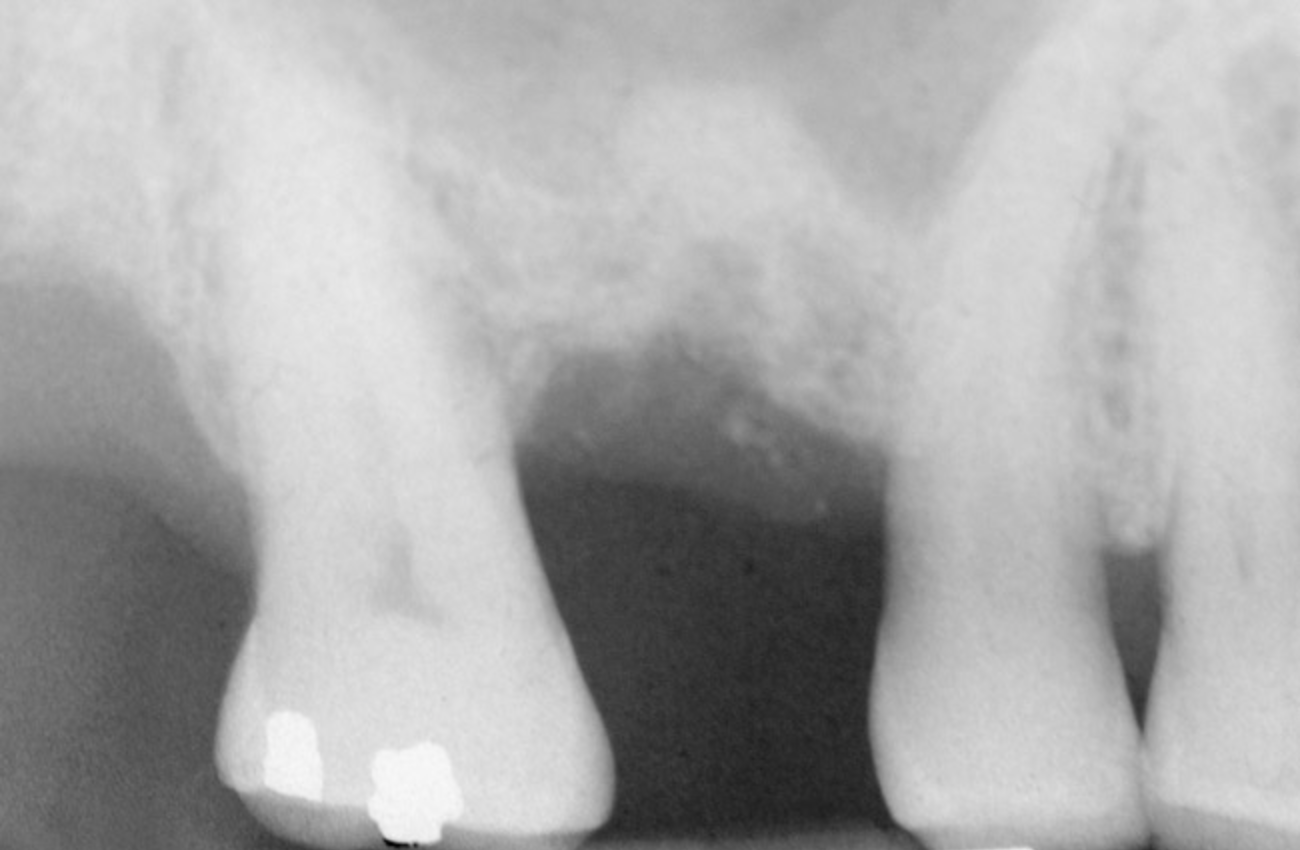

Figure 8  At site No. 13 the second bicuspid had a hopeless prognosis; it was to be extracted and replaced with an implant after a transcrestal sinus floor elevation.

Figure 8

Figure 9: After the extraction, a 2.1-mm twist drill was used to drill within 1 mm of the subantral floor. A guide pin was placed and a radiograph was taken to ascertain if the drill stopped within 1 mm of the subantral floor.

Figure 9